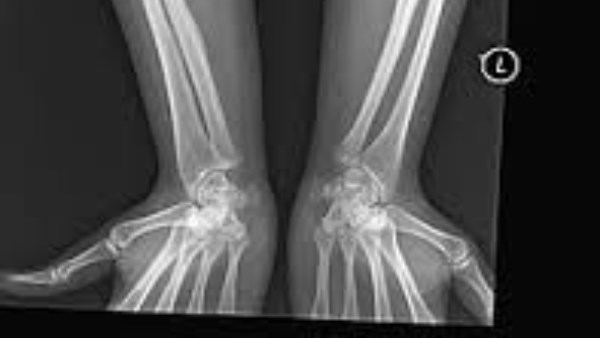

يُعرف أيضًا باسم مرض تكون العظم الناقص، وهو اضطراب وراثي يصيب النسيج الضام منذ الولادة ويستمر مدى الحياة.

يتميز المرض بهشاشة العظام وسهولة تكسرها، إضافةً إلى تشوهات عظمية ومشكلات صحية أخرى تتراوح بين الخفيفة والشديدة.

ينتج المرض عن نقص إنتاج الجسم للبروتين الكولاجين أو إنتاجه بشكل غير صحيح، وهو البروتين المسؤول عن تكوين العظام والجلد والعضلات والأوتار.